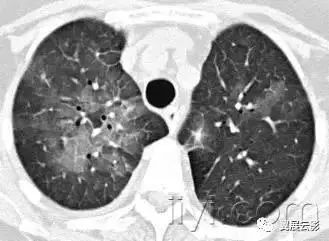

十八、小叶中心性:

解剖:小叶中心性用于描述次级肺小叶的支气管血管束中心区域。病理学上也用这一术语描述终末小支气管远端,位于呼吸性细支气管和肺泡管中心的病变。

CT:正常次级肺小叶中心的点状或者线状的密度增高影,胸膜下25px范围内最明显,代表小叶内的动脉,直径约1mm。

小叶中心性异常包括(1)结节(2)树芽征,提示小气道病变(3)由于临近间质的增厚或者浸润导致小叶中心结果更加清晰(4)小叶中心性肺气肿导致的异常低密度。

附图为小叶中心性肺气肿